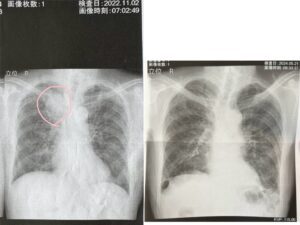

実は以前、おじいちゃんは肺がんが見つかり、ステージ4だと言われました。しかし、初めてコスプレをした翌日から歩き出し、酸素チューブが不要になり、外出までできるようになったといいます。おじいちゃんの身に起こった奇跡に驚いたと話す雷さん。